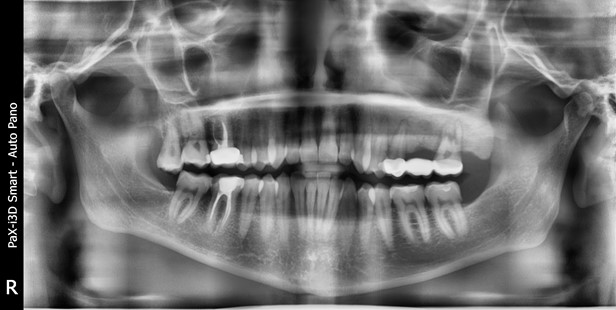

Это довольно печальный случай пожилого пациента. Внизу в челюсти (да и слева — буква R означает правую сторону челюсти с точки зрения пациента) вы можете увидеть непрорезавшиеся зубы.

Сверху временные, то есть молочные зубы, снизу постоянные. Вот подробный пост, как это устроено и какие особенности лечения детей вызывает. Здесь важно то, что пациент в возрасте около 60 лет всё ещё имеет несколько непрорезавшихся зубов.

Пациент из региона, в молодости денег на поездку в Москву или Европу для лечения у него, очевидно, не было, да и про достижения науки там вряд ли знали достаточно. Советский врач на месте сделал лучшее из возможного: когда молочные зубы износились, поставил сначала какую-то временную конструкцию, а потом, позже, когда пациент дорос до своего номинального размера, установил постоянную большую мостовидную конструкцию, которую вы тоже видите.

Сейчас тянуть зубы бесполезно, они давно уже живут в толще челюсти. Тем не менее вмешательство всё же нужно. Мост кончается. На таких больших конструкциях часто страдает точность. Слева в заднем отделе конструкция потеряла геометрию, там не было хорошей посадки — и образовался рецидив кариеса под металлом. Можно было санировать очаг и снова вернуть всё как было, но пациент хотел комфорта на всю оставшуюся жизнь. Поэтому протезирование. То есть мы вместо одной большой конструкции поставили несколько поменьше независимых, что в перспективе означает очень высокую точность и совершенно другие нагрузки. Вот рассказ про эту разницу, он вам пригодится, если ваши родители потеряют зубы.